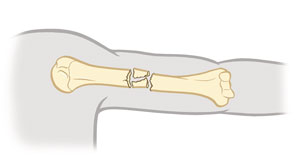

Comminuted fracture

The bone is broken into 3 or more pieces.